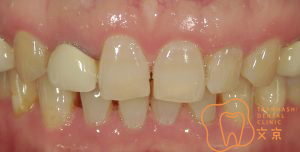

■前歯に後悔、、、

■保険の前歯を直したい

■前歯が折れてしまった、、、